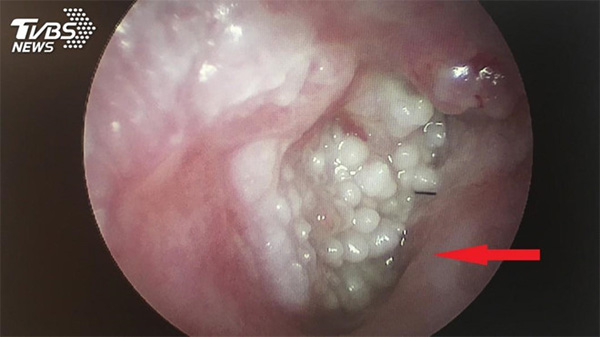

Các bác sĩ phát hiện trong lỗ tai của người đàn ông có nhiều mụn thịt mọc chi chít. Chúng lấp lỗ tai gây ảnh hưởng đến thính lực.

Những nốt sùi mào gà trong tai cụ ông họ Hoàng. Ảnh: TVBS.

Bác sĩ Ngô Thiệu Khoan, khoa Tai Mũi Họng, Bệnh viện Nam Đầu, cho hay sau khi dùng ống soi tai, các bác sĩ phát hiện trong lỗ tai của người đàn ông này có nhiều mụn thịt mọc chi chít. Chúng đã lấp toàn bộ lỗ tai nên ảnh hưởng đến thính lực.

Những mụn thịt này được chẩn đoán là sùi mào gà - một bệnh xã hội thường gặp ở vùng sinh dục. Điều này khiến bác sĩ Ngô rất bất ngờ và tò mò vì đây là lần đầu tiên ông gặp một bệnh nhân bị sùi mào gà trong lỗ tai.